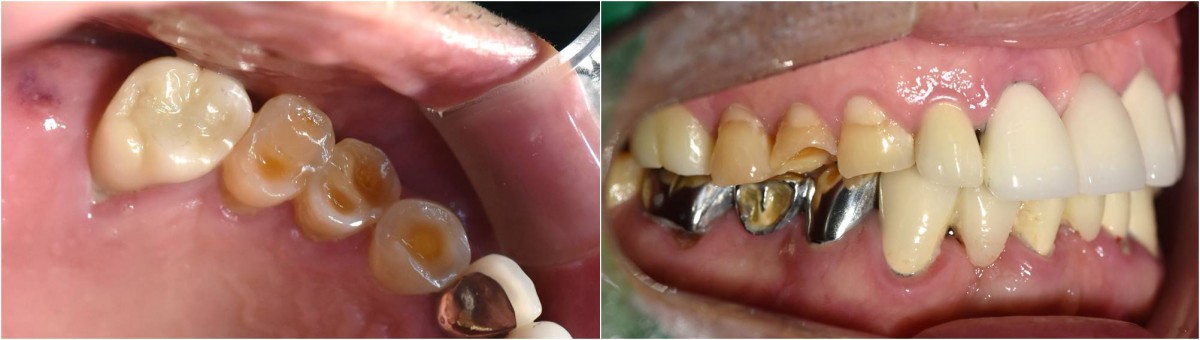

Socket Lift and Implant Placement in the right maxilla.

<GCacg> A 56-year-old male patient complained of pain in the right upper and lower jaws. And he wanted the upper first molar to be pulled out first.